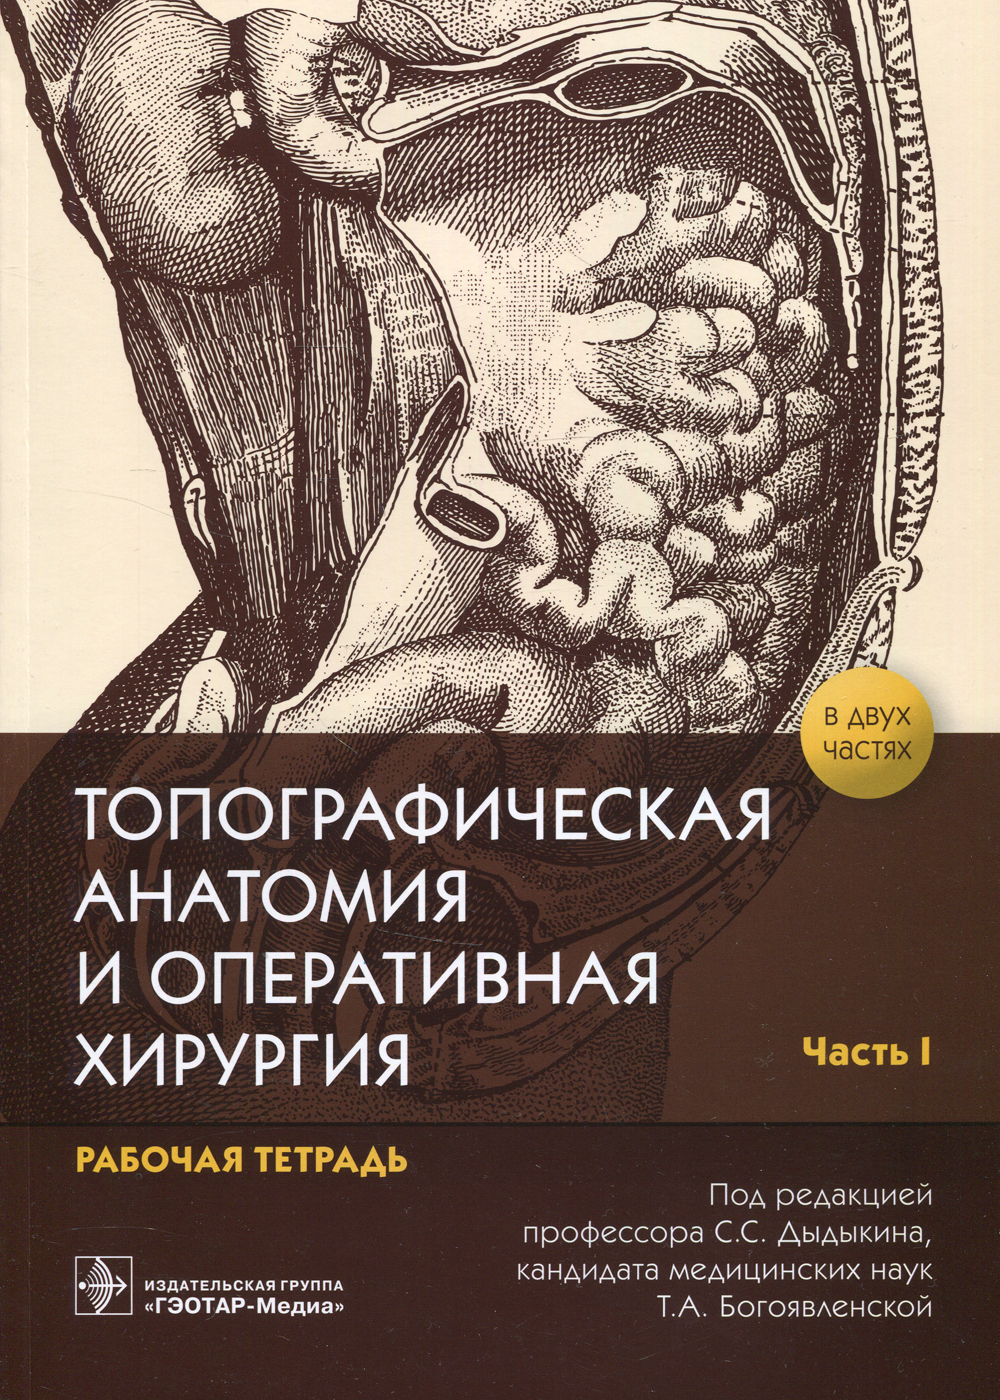

Руководство к практическим занятиям является результатом работы сотрудников кафедры оперативной хирургии и топографической анатомии Сеченовского Университета и позволяет совершенствовать процесс обучения студентов основным элементам оперативной техники.

Руководство к практическим занятиям является результатом работы сотрудников кафедры оперативной хирургии и топографической анатомии Сеченовского Университета и позволяет совершенствовать процесс обучения студентов основным элементам оперативной техники.

Технические характеристики

ИздательствоГЭОТАР-Медиа

Год выпуска2022

Тип обложкиМягкая обложка

Автор на обложкеНет автора

ISBN978-5-9704-6447-2

Тип книгиПечатная книга

Язык изданияРусский

Количество страниц56

Тип бумаги в книгеОфсетная

Формат издания70x100/16

Тип изданияОтдельное издание

Предмет обученияМедицина

Целевая аудитория учебной литературыУчащимся

Номер части учебного материала2

Всего частей учебного материала2